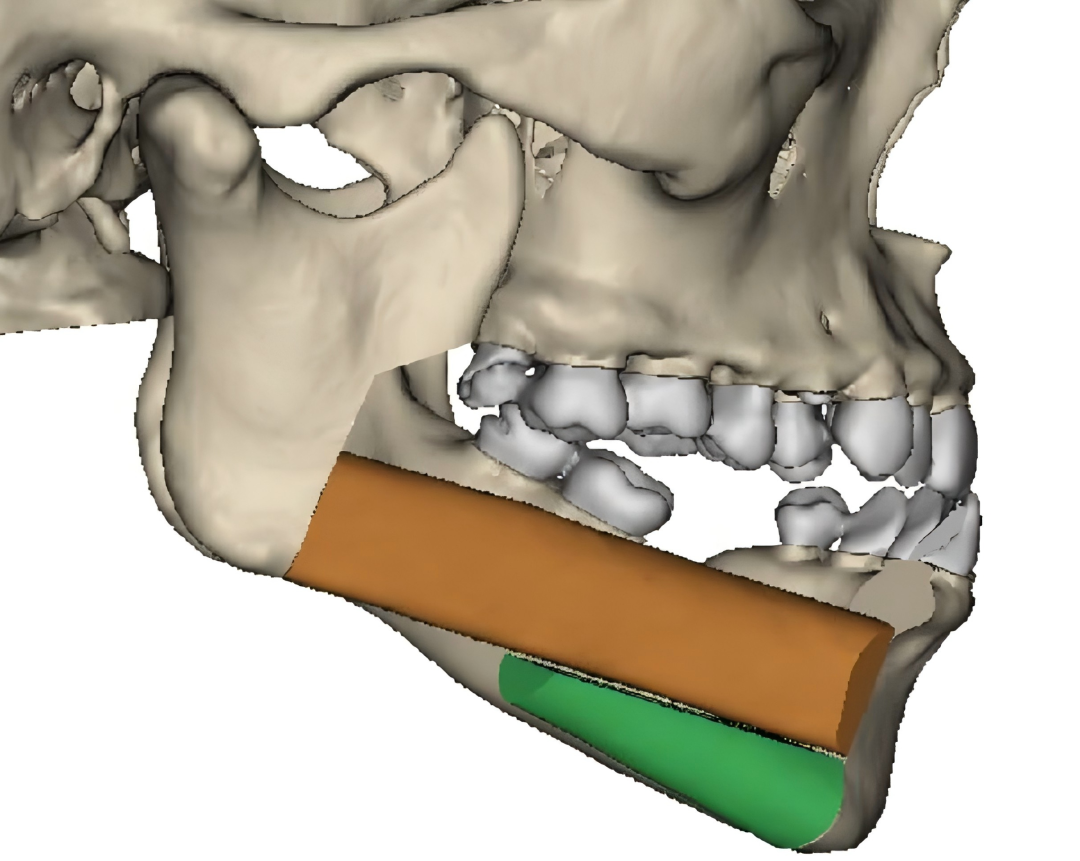

3.颌骨缺损精准重建

针对肿瘤、放疗或药物等因素导致的颌骨病变,以及在大范围切除术后造成的骨缺损问题,科室开展数字化(计算机辅助设计、3D打印)引导下的游离腓骨肌皮瓣移植术,实现颌骨的精准重建;并创新开展“移植腓骨同期种植”技术,在恢复面容外貌美观的同时,更有效重建咀嚼功能,全面提升患者生活质量。此项综合重建技术难度高,目前在省内能常规开展的医院屈指可数,整体水平达到国内前沿、省内先进。

科室自2007年起开展血管化游离骨瓣重建颌骨缺损手术,历经十余年技术迭代,实现了从单段到多段截骨、从单侧重建到双侧重建、从模型辅助到数字化设计与3D打印,从单纯骨组织修复到移植骨同期种植恢复咀嚼功能。每一步都紧跟前沿,每一次升级都只为更精准的治疗,使众多患者术后得以重返社会、重返生活。